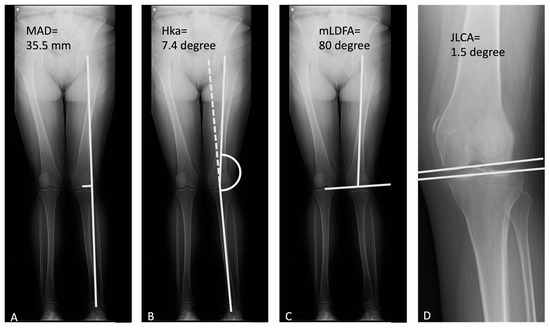

| MAD (mm) | −28.77 ± 12.98 | −9.45 ± 7.36 * | −14.6 ± 8.7 * |

| Hip-knee angle (degree) | 7.64 ± 3.62 | 2.58 ± 1.93 * | 3.2 ± 1.63 * |

| JLCA (degree) | 2.35 ± 1.48 | 1.75 ± 1.61 | 1.3 ± 0.83 * |

| mLDFA (degree) | 83.51 ± 3.48 | 92.01 ± 3.41 * | 90.2 ± 2.77 * |